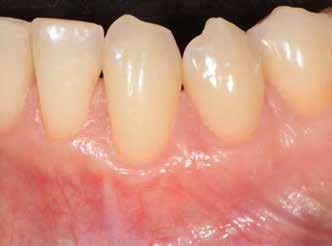

Szondázásra fellépő jelentős vérzés az 12 implantátum körül.

inflammatorikus IL-1β, IL-6 és IL-8 citokinek szintjét csökkentette, mind az olyan klinikai paramétereket, mint a plakkindex, a szondázási mélység, a szondázásra jelentkező vérzés és a sulcusváladék mennyisége. A placebocsoportban vizsgált implantátumok 20%-a körül szűnt meg a periimplant-mucositis, míg a probiotikummal is kezelt implantátumok körüli szövetek 74%-a vált gyulladásmentessé.

M. Galofré 2018-ban megjelent kutatásában az oki parodontális terápia hasznos kiegészítőjeként foglal állást a Prodentis probiotikum kombináció mellett. Periimplant-mucositis és periimplantitis esetében is jelentős javulást tapasztalt a vizsgált klinikai paraméterekben: a szondázási tasakmélység átlagosan 0,5 mm-es javulást mutatott a probiotikummal kezelt csoportban a placebocsoportban mért átlagos 0,2 mm-hez képest. A plakkindex esetében 39% javulás volt tapasztalható a placebocsoport 23%-os értékével szemben, a szondázásra jelentkező vérzés esetében 52%-kal kevesebb helyen jelentkezett vérzés, míg a placebót kapó csoportban ez mindöszsze 16% volt. A periimplantáris baktériumflóra összetételében nem tapasztalt ennyire szembetűnő változásokat, azonban a

Szájhigiéniés instruálás-motiválás, GBT-kezelés és Prodentis probiotikum kombináció, 4 hónap múlva

P. gingivalis sulcusváladékban mért szintje így is szignifikánsan csökkent.

Hiroaki Tada japán szerző 2018-ban megjelent írása4 szintén alátámasztja a fenti bekezdésben említetteket. Nem tapasztalt változást a parodontopatogén baktériumok mennyiségében, azonban az olyan klinikai paraméterek, mint a szondázásra jelentkező vérzés (53% vs. 37%), illetve a tasakmélység csökkenése kedvező irányba változtak.

Saját gyakorlati tapasztalataim alapján a klinikai paraméterek javulása egyértelműen látható. Kevesebb a szondázásra jelentkező vérzés, csökken a tasakmélység, kevesebb plakk borítja a fogak és implantátumok felszínét. A parodontopatogén baktériumok számának meghatározása rendelőnkben nem bevett gyakorlat, azonban mind a szék mellett tapasztalt objektív paraméterek, mind a páciensek szubjektív visszajelzései alapján a Prodentis probiotikum kombináció hasznos kiegészítője az oki parodontális terápiának.